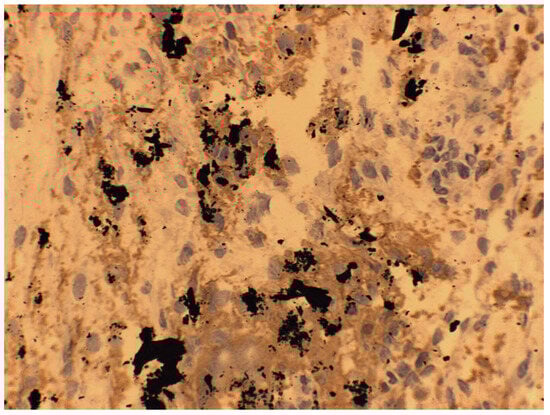

7. Macroscopic Observations of Interacted Surfaces of Removed Implants—Author Observations